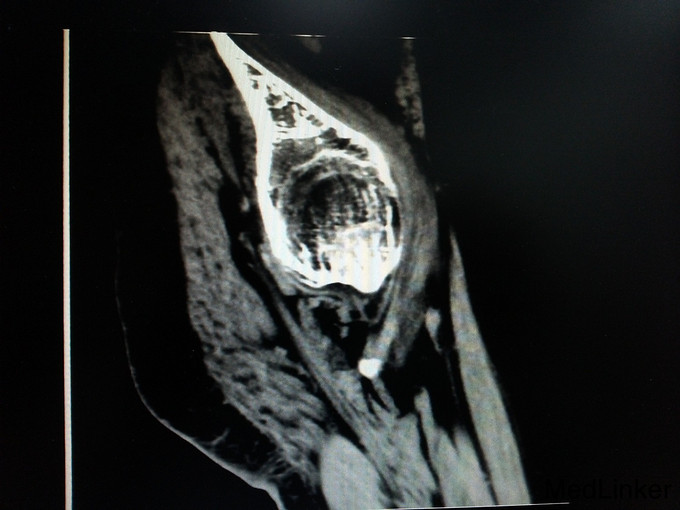

诊断:强直性脊柱炎(累及双侧髋关节) 患者腰骶部活动受限,影像学提示患者双侧骶髂关节间隙消失,且患者HLA—B27异常,强直性脊柱炎诊断明确。患者双髋关节间隙消失,活动度丧失,累及髋关节诊断明确。具有明确手术指症。患者既往关节鳞屑病,现控制稳定,经皮肤科会诊后排出手术禁忌症。由于经济稳定,患者及家属决定分次手术,本次手术暂行右侧人工全髋关节置换术。

讨论: 经验:强直性脊柱炎累及双髋的患者行全髋关节置换术时,显露及找到髋臼是手术的重点和难点。 1.显露。由于髋关节强直,失去活动度,助手在不能旋转大腿,造成显露困难。我们的做法是先充分显露小粗隆,沿小粗隆上方约2cm处截骨(一般常规于小粗隆上方0.5-1cm处截骨),充分离断头颈部,此时助手可通过内旋患肢,充分显露。下一步再按常规行小粗隆上截骨。 2.清除瘢痕组织。此类患者由于长期髋部强直,活动受限,周围往往会形成瘢痕挛缩,多以内收肌紧张常见。故显露的过程需彻底清除周围瘢痕组织。术中安装假体后测试关节各方西活动,若内收肌紧张,需行内收肌松解。 3.找髋臼。由于强直性脊柱炎累及髋关节需行关节置换的患者,往往头与髋臼已经发生融合,术中很难判断髋臼。若贸然凿除所谓的股骨头,很可能会破坏髋臼壁。故找髋臼时性循序渐进,逐渐凿骨找到髋臼。CT片显示头与髋臼底之间仍有间隙存在,故可推断圆韧带仍存在,这也是这类患者的特点。故逐渐凿除股骨头时,到达圆韧带的层面时就找到了髋臼底。此时可开始磨钻磨锉髋臼。从小号开始依次增大号数。 4.骨质。强直性脊柱炎的患者因长期服用激素类药物,骨量丢失较正常人较多,故髋臼骨质疏松明显,所以磨搓髋臼时需反转,防止骨量过度丢失,磨穿髋臼。 不足:1.术中由于患者左髋强直,摆放手术体位受限,不能维持身体中立位,身体后仰,术中安放臼杯时未能把握合适的前倾角度。 2.假体的选择。由于术前未认真评估股骨髓腔的形态,导致术中按常规选择股骨假体柄后,出现假体柄打入困难。该患者股骨髓腔形态呈烟囱型,最好选择直柄,打入后可更贴合,方便骨长入。